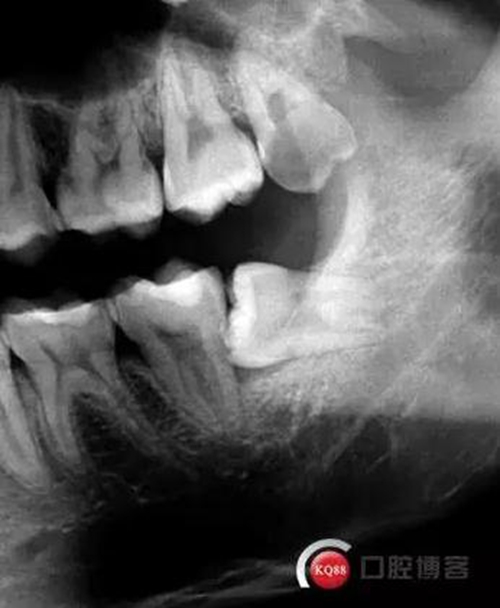

檢查:口內(nèi)可見(jiàn)38未完全萌出,無(wú)松動(dòng),周?chē)例l顏色正常,叩診(—)觸診(—),X線顯示近中阻生,雙根

診斷:阻生齒

治療方案:建議拔除

處理:治療計(jì)劃及費(fèi)用已說(shuō)明,知情同意后,排除拔牙禁忌癥:口腔黏膜消毒,左下頜阻滯麻醉成功后,切開(kāi)翻瓣,渦輪機(jī)去除近中阻力,向近中挺出患牙,拼對(duì)牙體完整,清創(chuàng),置明膠海綿,縫合傷口,咬棉球壓迫止血